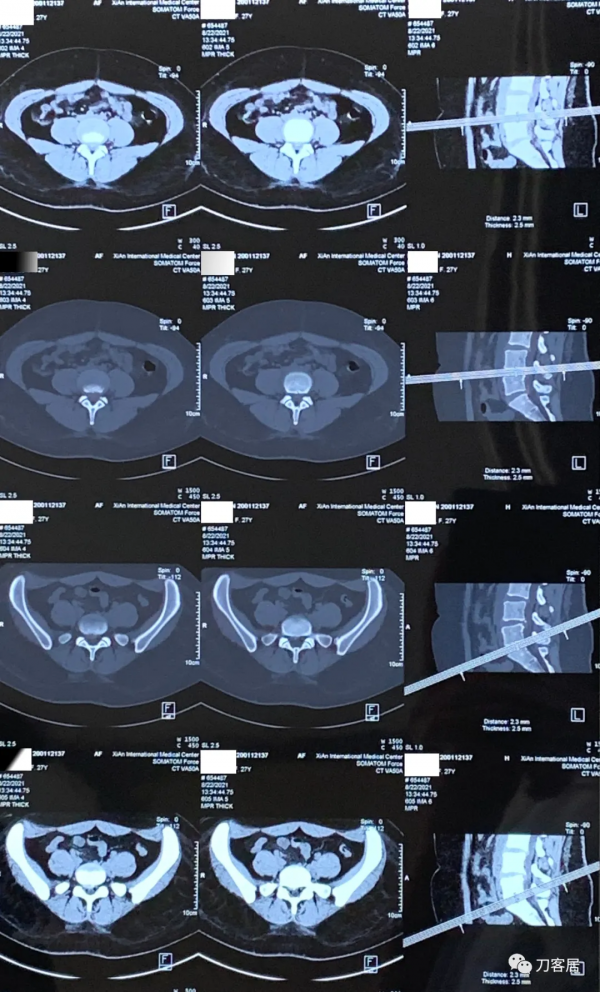

圖8. 20210822術前腰椎CT橫截面掃描,提示腰4-5椎間盤突出,右旁中央型,腰椎管狹窄,腰5骶1椎間盤突出,右旁側型。

圖9. 20210830術後6天拍攝的腰椎正側位X線片,可見腰5雙側椎板均已切除減壓,所以, 這個手術應該是做的腰4-骶1後路全椎板切除減壓,腰4-骶1椎間融合器植骨融合, 每個間隙兩枚融合器,腰4-骶1後外側植骨融合內固定術。應該是典型的PLIF手術。

圖10. 20210831術後7天拍攝的腰椎側位X線片及右側股骨正側位X線片,顯示術後內固定位置良好,但不知道為啥當時給拍了右側股骨正側位X線片,也許可能術後右大腿部有比較明顯的疼痛吧。應該是8月30日到31日這兩天,患者的下肢症狀應該有反覆。否則不應該做腰椎手術,拍股骨X線片的。